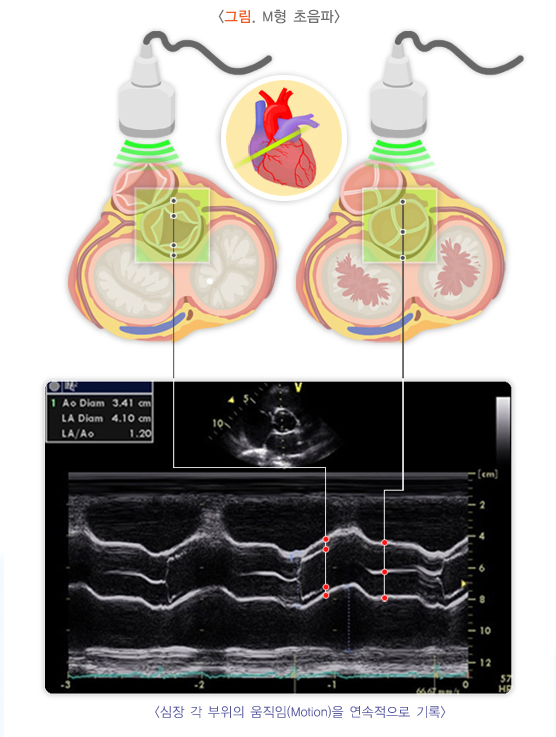

4. 초음파 도플러 검사

- 정맥 혈류 평가

초음파 도플러 검사를 통해 혈관 내 혈류 방향, 속도, 정맥 판막의 기능 이상 여부를 정밀하게 확인할 수 있습니다. - 심부정맥 및 표재정맥 상태 확인

심부정맥 혈전증 여부, 혈류 역류, 혈관 폐쇄 등을 진단합니다. - 거미정맥류 주변 혈관의 연결 상태 파악

거미정맥류가 진성 하지정맥류와 연관되어 있는지, 혈관망이 어떻게 연결되어 있는지 평가합니다.